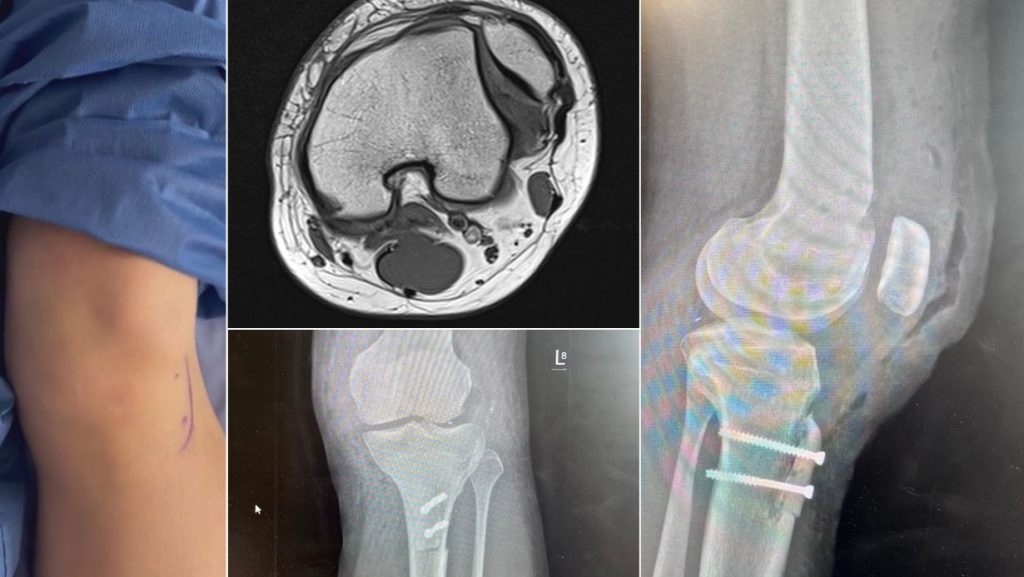

REKONSTRUKCJA STAWU RZEPKOWO-UDOWEGO

Lekarze Oddziału Chirurgii, Urologii i Ortopedii Dziecięcej przeprowadzili po raz pierwszy w naszym województwie nowatorski zabieg rekonstrukcji stawu rzepkowo-udowego – tzw. trocheoplastykę (korekcję dysplazji stawu rzepkowo-udowego). Zabieg został wykonany jednoczasowo z uwolnieniem rzepki oraz jej obniżeniem poprzez osteotomię guzowatości kości piszczelowej. Całość została uzupełniona o rekonstrukcję więzadła rzepkowo-udowego przyśrodkowego (MPFL).